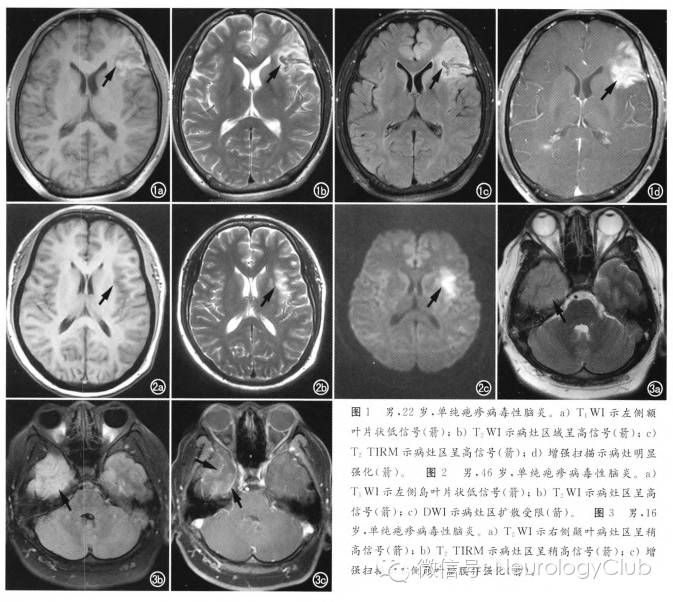

在各种病毒所致脑炎中,单纯疱疹病毒性脑炎的影像学最具特征性,可归纳为:①病变多先累及单侧或双侧颞叶,部分病例可向额叶或枕叶发展,单独发生于额叶、枕叶及顶叶者少见;②病变均与豆状核之间界线清楚,凸面向外,如刀切样,称刀切征,许多学者认为这是本病最具特征性的表现;③CT平扫呈片状不规则低密度,,MRI检查呈长T1、T2片状高信号,以T2WI上病变显示最为清楚;④不增强或线样脑回状增强。主要位于病变的边缘部分。增强与否可能与病变的严重程度有关,因为广泛的血管炎和脑组织灶性坏死是出血强化的病理基础;⑤严重者可有占位效应。

(图3:单纯疱疹病毒性脑炎)